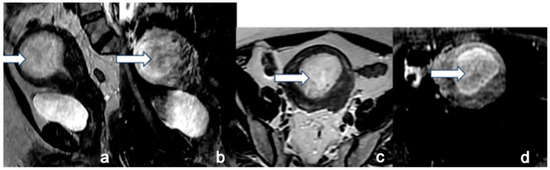

5.3. Magnetic Resonance Imaging (MRI)

- Maheshwari, E.; Nougaret, S.; Stein, E.B.; Rauch, G.M.; Hwang, K.-P.; Stafford, R.J.; Klopp, A.H.; Soliman, P.T.; Maturen, K.E.; Rockall, A.G.; et al. Update on MRI in Evaluation and Treatment of Endometrial Cancer. RadioGraphics 2022, 42, 2112–2130. [Google Scholar] [CrossRef] [PubMed]

- Neves, T.R.; Correia, M.T.; Serrado, M.A.; Horta, M.; Caetano, A.P.; Cunha, T.M. Staging of Endometrial Cancer Using Fusion T2-Weighted Images with Diffusion-Weighted Images: A Way to Avoid Gadolinium? Cancers 2022, 14, 384. [Google Scholar] [CrossRef] [PubMed]

- Nougaret, S.; Horta, M.; Sala, E.; Lakhman, Y.; Thomassin-Naggara, I.; Kido, A.; Masselli, G.; Bharwani, N.; Sadowski, E.; Ertmer, A.; et al. Endometrial Cancer MRI staging: Updated Guidelines of the European Society of Urogenital Radiology. Eur. Radiol. 2019, 29, 792–805. [Google Scholar] [CrossRef]